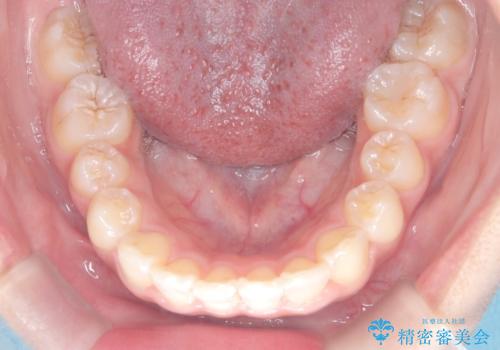

マウスピース矯正で前歯のガタツキを改善! ワイヤー矯正併用でかみ合わせもしっかり治します

- 前歯のガタツキが気になると来院されました。

マウスピース矯正治療を選択しました。

この症例では、奥歯のかみ合わせの改善を目的にワイヤー矯正を併用しました。奥歯のかみ合わせをより緊密にするため、また短期間に治療するためにはワイヤー矯正が適していることがあります。